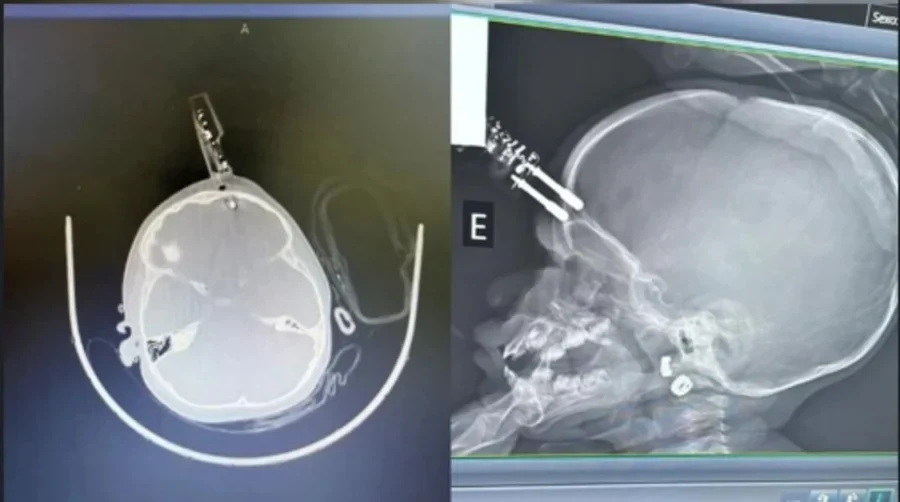

Bebê de 1 ano cai da cama e fica com carregador cravado na testa em MG

Uma menina de 1 ano passou por cirurgia de urgência, na terça-feira (13/1), após cair da cama e ter um carregador cravado na testa em Divinópolis (MG). De acordo com os médicos, a criança segue em observação e, até o momento, não apresenta sinais de sequelas neurológicas.

O neurocirurgião Bruno Castro, responsável pelo atendimento, informou que a mãe do bebê havia ido ao banheiro no momento do acidente. A criança estava com o carregador na mão quando caiu da cama, e acabou com o objeto cravado na cabeça.

A criança foi levada para a sala de cirurgias onde passou por procedimentos de limpeza, retirada do objeto, lavagem, fechamento e reconstrução da área atingida.